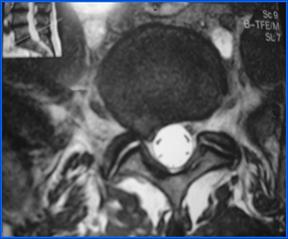

1.- Paciente de 50 años, con HNP L5 – S1, que no respondió a tratamiento conservador, incluyendo antiinflamatorios, fisioterapia y kinesioterapia, por 8 semanas, incluyendo un corticoide peridural por lo que se decidió realizar Nucleotomía Percutánea Automatizada más Apoyo Artroscópico (lo que permite retirar mayor cantidad del tejido herniado).

En este caso se logró una remisión completa del dolor y volvió a trabajar a los 12 días.